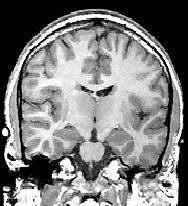

![]() |

| Coronal MR scans from a chronic schizophrenic (above) and normal comparison subject (below). Note increase in CSF in left amygdala-hippocampal complex. Images courtesy of Schizophrenia Research Project and Psychiatry Neuroimaging Laboratory, Harvard University, Boston. |

Parkison was diagnosed with AIDS in 1992 and, after he was jailed, an MRI scan showed brain lesions. In an HIV-positive patient, these lesions can lead to poor impulse control and a lack of judgment, according to the psychiatrist who examined Parkison (SFGate.com, May 1, 1998).